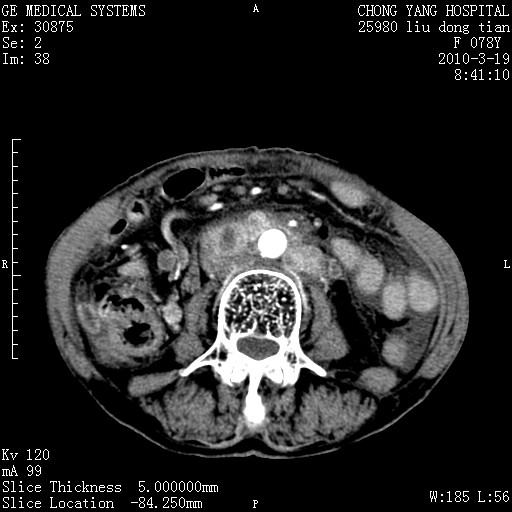

标题: CT25199:F 78Y 腹胀半年 消瘦乏力 [打印本页]

胆囊壁增厚并明显强化,胆囊癌伴多发转移瘤可能性大,淋巴瘤不除外,右肾囊肿,胸腹水.

考虑nhl,肝、脾、腹膜腔及腹膜后多发淋巴结受侵,腹水,右肾囊肿,慢性胆囊炎,右侧少量胸腔积液。

胰头有肿块形成,胰头ca伴肝脾、腹膜腹膜后转移

胆囊有软组织影有强化,支持胆囊癌,肝脾、腹膜后淋巴结转移。

nhl的淋巴结多围绕主动脉,而且主动脉会移位,所以不考虑nhl。

分开来讲:肝左叶、尾叶病灶有不均强化像肝癌;

脾脏病灶无强化,像多发囊肿或淋巴管瘤,不除外淋巴瘤(低强化);

胆囊增生性病变:胆囊癌,腺肌增生症,慢性胆囊炎;

肝门、胰腺头、腹膜后多个团块: 淋巴瘤,转移;

腔静脉肝内段细小有无布加可能?

一元论最好了 淋巴瘤所致改变; 胆囊癌转移不像,胆囊周围肝组织清晰,肝癌淋巴结转移?三元论都不止。

胰头ca伴肝脾、腹膜腹膜后转移!

最后报的胰头癌多发转移,脾脏单独考虑囊肿或淋巴管瘤。